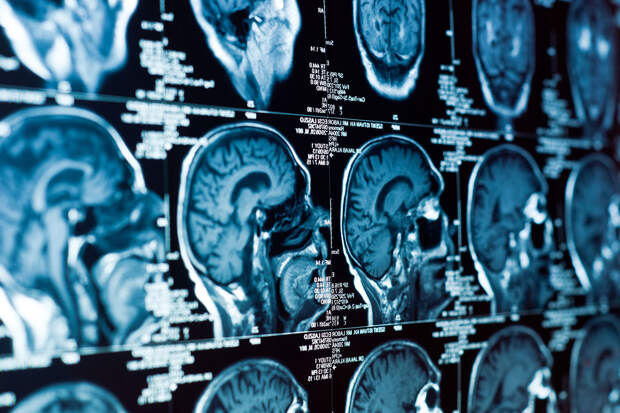

Ученые выяснили, что у пожилых людей с жесткими артериями чаще возникают повреждения нервных клеток мозга. Результаты исследования опубликованы в журнале Alzheimer's & Dementia (A&D).

В исследовании приняли участие 570 пожилых людей, которые не жаловались на проблемы с памятью или мышлением. Ученые хотели понять, как состояние сосудов влияет на ранние признаки повреждения мозга и когнитивные функции.

Результаты показали, что у участников с более жесткими артериями когнитивные показатели были ниже. Чаще всего наблюдались проблемы с эпизодической памятью — способностью вспоминать события. Также изменения в сосудах коррелировали с ухудшением оперативной памяти и скорости обработки информации. Особенно выраженные нарушения наблюдались у людей, у которых сочетались высокий уровень NfL и повышенная жесткость сосудов.

Авторы работы подчеркивают: старение мозга связано не только с гибелью нейронов, но и с состоянием сосудов, которые обеспечивают их питание.